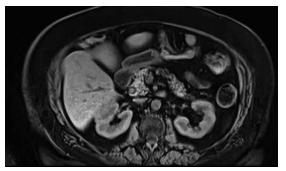

Mulher de 55 anos, com antecedente de gastroplastia

em Y de Roux, com colecistectomia há 1 ano por obesidade, evolui com dor em hipocôndrio direito, colúria e

icterícia.

Exames laboratoriais mostram bilirrubina total de 5,8 mg/dL (direta 4,4), fosfatase alcalina de 690 U/L e leucocitose discreta.

Realizou-se uma ressonância, conforme mostra a imagem a seguir.

(Arquivo pessoal; imagem usada com autorização)

Em face do exposto, assinale a alternativa correta.

Exames laboratoriais mostram bilirrubina total de 5,8 mg/dL (direta 4,4), fosfatase alcalina de 690 U/L e leucocitose discreta.

Realizou-se uma ressonância, conforme mostra a imagem a seguir.

(Arquivo pessoal; imagem usada com autorização)

Em face do exposto, assinale a alternativa correta.